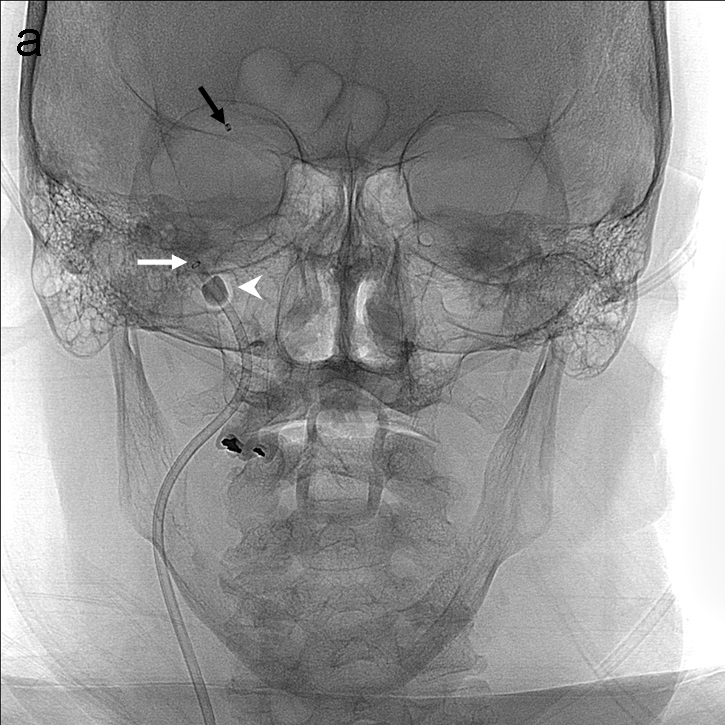

Se realiza una serie a través del catéter balón que demuestra una recanalización parcial del segmento M1 proximal con apertura de arterias lenticuloestriadas y persistencia oclusión de segmento M1 distal de ACM derecha (imagen 3). Se decide cambiar de estrategia y usar la técnica SAVE con Catalyst 5, Trevo Pro 18, Asahi Chikai 0.014’’ y Catch 6 x 30 mm.

La técnica SAVE consiste en combinar stentriever (colocándolo con el trombo en su tercio proximal) y un catéter de aspiración (en contacto con la porción proximal del trombo) y realizar el pase actuando como una unidad, ofreciendo una captura distal (stentreiver) y proximal del coágulo con el catéter de aspiración (imagen 4). Se retiran simultáneamente bajo aspiración con bomba y manual a través del catéter balón.

Se vuelve a realizar una serie a través del FlowGate2, en este caso demostrando una apertura completa de la ACM y sus ramas hemisféricas derechas, TICI 3 (imagen 5).